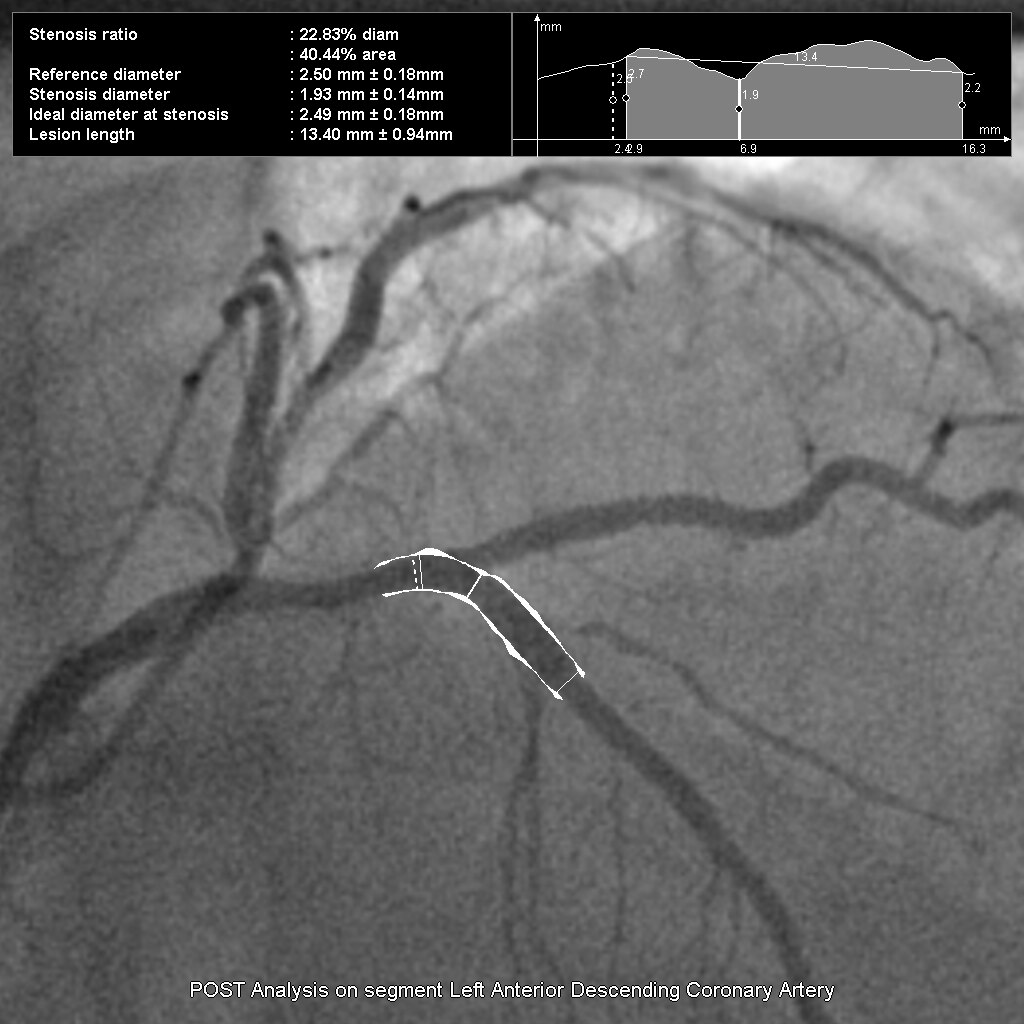

Клинические приложения

- InnovaSpin — оптимальная проекция сосуда за одну инъекцию контраста. Клиническое приложение для ротационной ангиографии Innova Spin позволяет увидеть всю камеру сердца и анатомию коронарных сосудов за одну съемку и с одной инъекцией контраста;